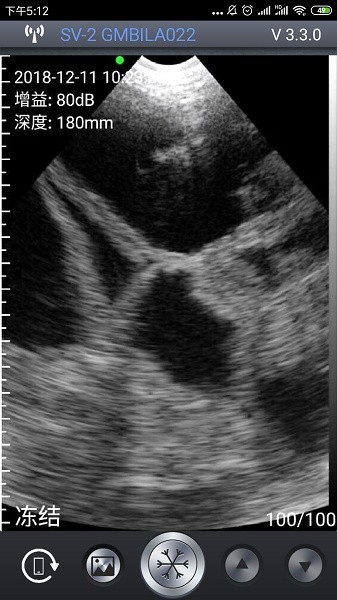

2、 成像精准:配套硬件协同工作,呈现高清晰度图像,辅助准确判断母猪怀胎情况。

2、实时图像显示:即时呈现超声扫描画面,便于快速查看与初步判断检测结果。

4、智能妊娠识别:基于深度学习算法自动判断母猪妊娠状态,提高诊断准确率。